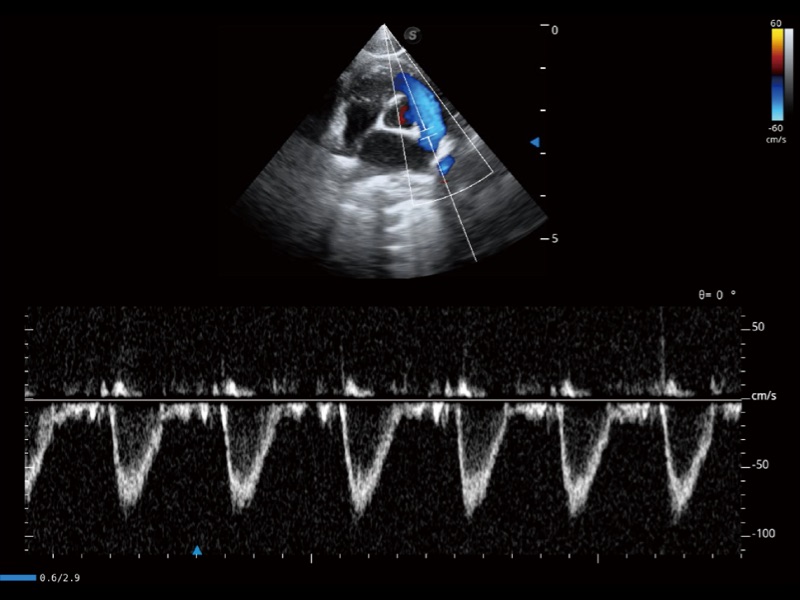

(猫)肺动脉血流频谱

(犬)左室长轴血流

(犬)髂动脉血流

(犬)四腔心

(犬)四腔心MQA